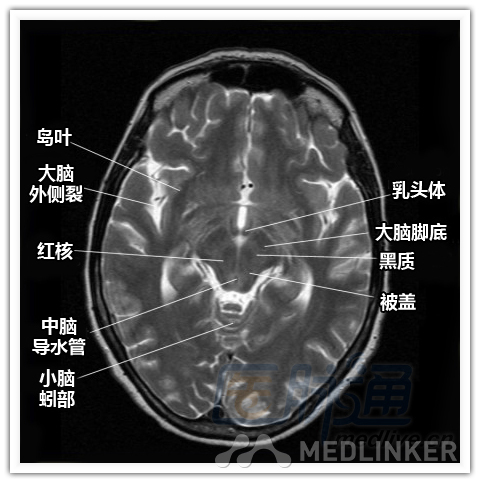

简明易懂的脑部断层解剖:横断位MRI(1)

本文将对不同横断位的脑部MRI图像进行标示,主要讲解内容是脑部基本解剖。脑部横断位解剖,尤其是内囊层面的影像学解剖一直是一大重点,一起来学习一下。 横断位图像顺序:由足侧至头侧 本文转载自医脉通。 声明:本文转载是出于提供更多信息以参考使用或学习、交流之目的,不用于商业用途。转载无意侵犯版权,如转载文章涉及您的权益等问题,请作者速来告知,我们将尽快做删除处理。